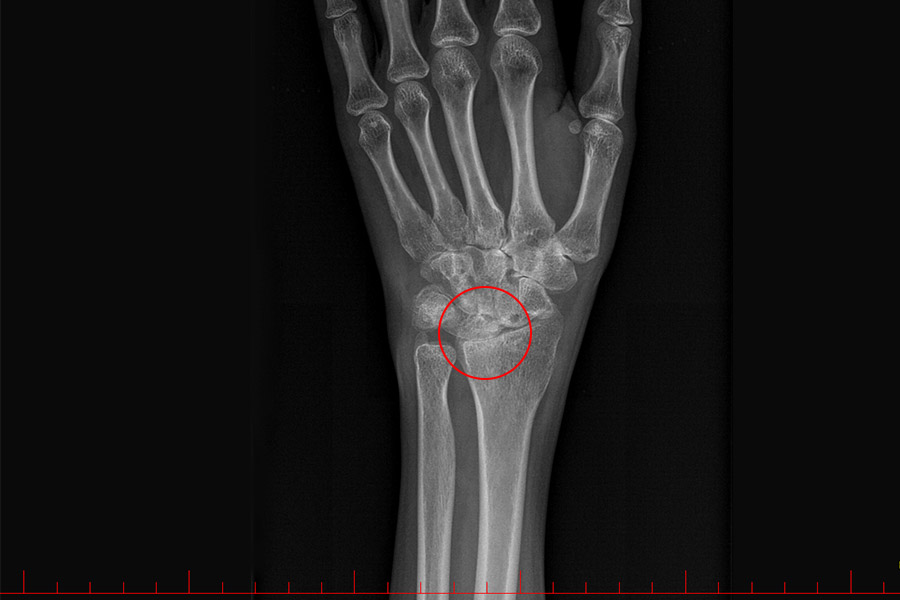

Choroba zwyrodnieniowa (nadgarstek)

Artrodeza

Artrodeza (inaczej: usztywnienie stawu) to metoda chirurgicznego leczenia zaawansowanej choroby zwyrodnieniowej stawów. Trwale znosi ruchomość w operowanym stawie, jednak dzięki